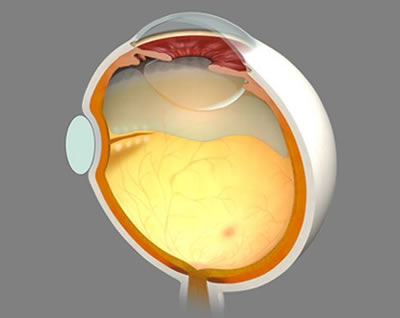

망막 박리란 망막이 안구의 내벽으로부터 분리되는 상태를 말합니다. 이는 망막이 안구의 기저층에서 분리되어 시세포의 영양 공급이 미비해지며, 결과적으로 시력 저하를 유발할 수 있는 심각한 안과 질환입니다.

- 열공성 망막 박리 : 가장 일반적인 형태로, 망막에 구멍이 생기면서 유리체의 액체가 이 구멍을 통해 들어가 망막을 들어 올리는 상황입니다. 대개 외상이나 고도근시 등으로 인해 발생합니다.

- 견인성 망막 박리 : 당뇨병성 망막병증이나 기타 망막 질환에 의해 흉터 조직이 형성되고, 이 조직이 망막을 당겨 들뜨게 만드는 것으로 발생합니다. 특히 유아기 또는 청소년에서 많이 발생할 수 있습니다.

- 삼출성 망막 박리 : 종양이나 염증 등에 의해 망막 아래에 체액이 쌓여 망막이 떨어지는 경우입니다. 이 상태는 망막 자체의 구멍이나 찢어짐 없이 발생할 수 있습니다.